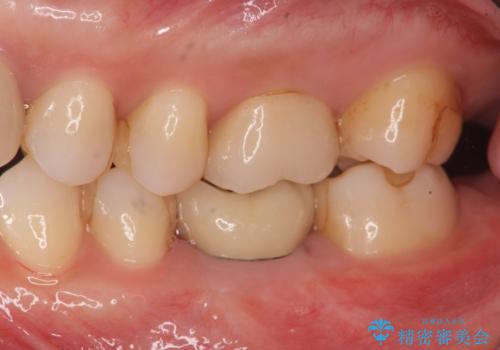

欠損部のインプラント補綴

- 失った奥歯にインプラント治療を受けたい、と希望され来院されました。

前後の歯を削らずに機能回復できるインプラントを用いて審美生、咬合機能の回復を計画します。

痛みや腫れもほとんどなくインプラント治療を終えられ、しっかり噛むことができるようになった。と治療結果に満足いただくことができました。